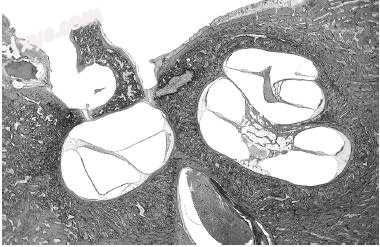

3.jpg

图-3. 典型的组织细胞增生症的肉芽组织可见于4岁男孩患有颞骨Letterer-Siwe病(×4)的乳突(M),中耳(ME)和岩尖(PA)的溶解性病变。